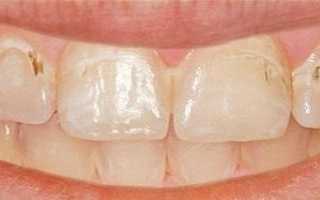

Признаки поверхностного кариеса.

<Нередко во время приема еды или употребления горячих (холодных) напитков человек чувствует некоторую болезненность зубов, которая быстро проходит. Считая ее незначительным признаком, или, принимая ее за индивидуальную реакцию зубов на раздражители, большинство не спешит обращаться к стоматологу. На самом же деле это и есть один из основных симптомов поверхностного кариеса.

Для поверхностного кариеса характерна слабовыраженная симптоматика. Дефект дентина незаметен при самостоятельном визуальном осмотре, а кратковременную болезненность, возникающую при контакте пораженного зуба с химическими или термическими раздражителями, больной воспринимает, как временное повышение чувствительности зубной эмали. Следует отметить, что при поверхностном кариесе боль проходит непосредственно после прекращения воздействия химического, механического или термического раздражителя.

При стоматологическом осмотре врач может отметить нарушение целостности зубной эмали пораженного зуба.

Определить наличие поверхностного кариеса можно только при тщательном стоматологическом осмотре. При визуальном осмотре заболевание проявляется в виде участка деминерализованной эмали, которая имеет желто-серый цвет.